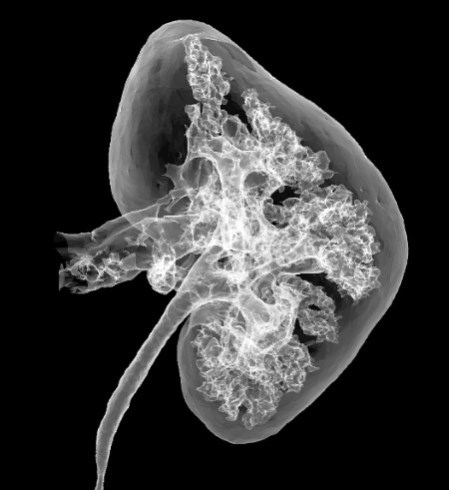

Иллюстрация к книге — Взламывая анатомию [image217.jpg]

Нефрон является основной структурно-функциональной единицей почки и образует ее тканевый каркас.